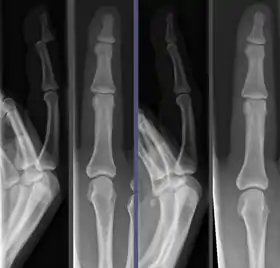

![]() Joint dislocation in the DIP of the third finger before (left images) and after (right images) reduction. | |

Because the process of reduction can briefly be intensely painful, it is commonly done under a short-acting anesthetic, sedative, or nerve block. Once the fragments are reduced, the reduction is maintained by application of casts, traction, or held by plates, screws, or other implants, which may in turn be external or internal. It is very important to verify the accuracy of reduction by clinical tests and X-ray, especially in the case of joint dislocations.